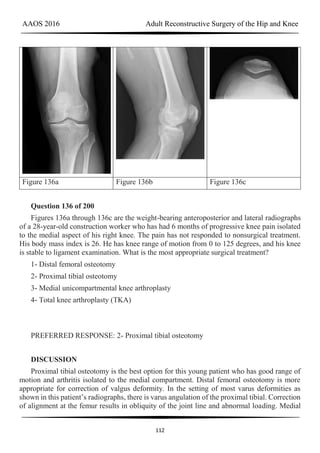

Figure 58 Figure 59a Figure 59b

RESPONSES FOR QUESTIONS 58 THROUGH 62

Total knee arthroplasty (TKA) is performed to address each condition shown in Figures

58 through 62b. Which complication is most commonly associated with each image?

Question 58 of 200

Figure 58

1- Nerve palsy

2- Skin necrosis

3- Flexion instability

4- Patellar instability

5- Anterior knee pain

6- Malalignment

PREFERRED RESPONSE: 1- Nerve palsy

Question 59 of 200

Figure 59a and Figure 59b

AAOS 2016 Adult Reconstructive Surgery of the Hip and Knee

49

PREFERRED RESPONSE: 4- Patellar instability

DISCUSSION

Figure 58 reveals a posttraumatic valgus deformity. Correction of valgus with lateral soft-

tissue release places tension on the peroneal nerve, resulting in an increased risk for nerve

palsy. Figures 59a (lateral view) and 59b (Merchant view) illustrate juvenile rheumatoid

arthritis with tibiofibular fusion and lateral patellar dislocation. Chronic patellar dislocation is

associated with contracture of the lateral retinacular soft tissues and increased risk for patellar

subluxation or dislocation after TKA. Extensor mechanism realignment, possibly including

tibial tubercle osteotomy and/or proximal soft-tissue realignment, may be required during

TKA to centralize the extensor mechanism. Figures 60a (anteroposterior [AP] view) and 60b

(lateral view) reveal a fused knee in full extension.